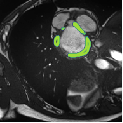

Despite their outstanding accuracy, semi-supervised segmentation methods based on deep neural networks can still yield predictions that are considered anatomically impossible by clinicians, for instance, containing holes or disconnected regions. To solve this problem, we present a Context-aware Virtual Adversarial Training (CaVAT) method for generating anatomically plausible segmentation. Unlike approaches focusing solely on accuracy, our method also considers complex topological constraints like connectivity which cannot be easily modeled in a differentiable loss function. We use adversarial training to generate examples violating the constraints, so the network can learn to avoid making such incorrect predictions on new examples, and employ the Reinforce algorithm to handle non-differentiable segmentation constraints. The proposed method offers a generic and efficient way to add any constraint on top of any segmentation network. Experiments on two clinically-relevant datasets show our method to produce segmentations that are both accurate and anatomically-plausible in terms of region connectivity.